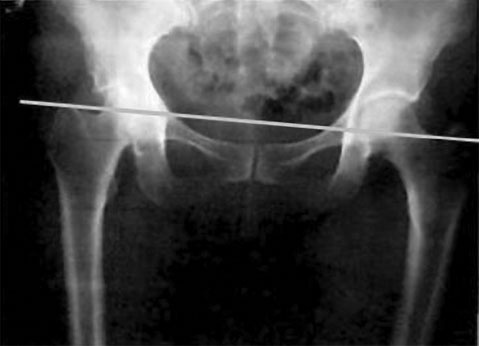

Человек ходит по Земле ногами и «питается» от нее теллурическими токами, заряжаясь электрической и магнитной активностью. Поэтому одна нога у него «плюс», а другая «минус». Соответственно, наши конечности имеют не только разный знак, но и разный вектор направления: одна нога (как и рука) притягивается к земле, а другая отталкивается, одна нога имеет направление вглубь тела, а другая – во внешнее пространство – тело идет на разрыв. И минимальный уровень такого дисбаланса неизбежен, поскольку обеспечивает необходимую разность потенциалов. Начальное равновесие тела зависит от положения тазобедренных суставов. Их симметрия обеспечивает баланс всей «ракеты». Иначе она не «полетит». В идеале вертикальная ось по фронтальной поверхности тела должна проходить строго между ногами, по срединной линии тела и переносице. Симметрию тазовых суставов во фронтальной плоскости (на виде спереди) можно увидеть на рис. 15. ![]() Рис. 15. Симметрия тазовых суставов А теперь сравните его с рис. 16 – горизонталь, идущая по ним, перекашивается к левой ноге. ![]() Рис. 16. Асимметрия таза Видно, что уровень левой стороны (реальной стороны человека) ниже, чем правой. Значит, левая нога больше опирается на землю. Именно здесь нас поджидает дисбаланс под названием «опорная нога». На опорную ногу при ходьбе приходится бо́льшая часть веса человека. И потому биомеханический рисунок тела соответствует рисунку «хиазма», который был известен еще античным скульптурам (рис. 17). ![]() Рис. 17. Хиазм на теле человека Он изображался стоящей фигурой человека, у которого тяжесть тела перенесена на опорную ногу. Поднявшемуся из-за этого бедру соответствует опущенное плечо, а другому, опущенному бедру – поднятое плечо. По законам физики любое действие вызывает противодействие, приводя к рождению компенсационных сил: чем сильнее мы опираемся на землю, тем сильнее она выталкивает опорную ногу, укорачивая ее и буквально затягивая вглубь таза. И все определяется работой «нейтральной зоны» системы левитации, находящейся в районе грудобрюшной диафрагмы, разделяющей тело на две ступени. Именно она, одновременно, и разъединяет, и соединяет обе половины тела невидимой связью. Когда зона левитации, где встречаются противоположные заряды, перестает работать, электромагнитный баланс нарушается. В случае усиления дисбаланса (рис. 18) укороченная левая нога начинает сильнее притягиваться к земле (серая стрелочка). В силу возникновения сил противодействия она начинает выталкиваться (черная стрелочка) и по диагонали выталкивать правое плечо. ![]() Рис. 18. Направления деформаций при синдроме «опорная нога» Выявить подобную асимметрию можно не только по уровню ягодиц, но главное и по уровню талии и бедер – в данном примере правый бок будет выше левого. В своей норме такие деформации свойственны «условно здоровому» человеку и практически не проявляются в теле. Как только система левитации закрывается, эти деформации начинают увеличиваться и приводить к сколиозам, ротациям и наклонам тела. Поэтому общая статика всегда определяется компенсационными реакциями тела на свое «заваливание» на опорную ногу в попытках удержать равновесие. Одним из главных требований к балансу тазовой области является симметрия крестца по срединной линии, делящей спину на две половинки. Если крестец смещен к левой или правой ягодице, начинаются сколиотические и ротационные подвижки позвоночника. Поэтому первое, чем занимается остеопат, – выставляет крестец строго по центру. Простыми приемами Осьмионики его можно выправить и самостоятельно. Главное, потом контролировать свою позу при сидении на стуле – не сидеть на одной ягодице, заваливая тело, не закидывать ногу за ногу, а держать тело ровно по центру промежности и ягодиц. Та же эталонная ось, идущая в саггитальной плоскости, должна идти по профилю тела человека через несколько ключевых точек: центр пятки, шарнир тазобедренного сустава, акромиальный отросток плеча (его головку) и центр наружного слухового прохода. Я назвала эту ось Гравитационной вертикалью (рис. 19). ![]() Рис. 19. Гравитационная вертикаль В физике она называется мировой осью или осью мира. Поэтому основной прием на осанку и носит название Ось мира. От нее и пошло название методики – Осьмионика (сходство с фамилией автора – случайность). Чтобы понять, как должно быть выстроено тело по Гравитационной вертикали, обратимся опять к строению ракеты. Ведь если она не будет стоять вертикально по отношению к Земле, она не взлетит. Вы считаете, что сравнение тела человека с ракетой некорректно, потому что ракеты летают вертикально, а мы передвигаемся по земле горизонтально? Действительно, все современные ракеты взлетают вертикально. Однако первая ракета, предложенная Циолковским, основоположником нашей авиации, делала разбег по земле и лишь потом взмывала в воздух. Свой труд «Космические ракетные поезда» К. Э. Циолковский опубликовал в 1929 году. И, не считая горизонтального взлета, все современные ракеты вобрали в себя основные принципы многоступенчатой ракеты Циолковского. Многоступенчатость ракеты – это в первую очередь рациональное использование ресурсов, экономия топлива. Точно так же происходит в нашем теле: его конструкция в виде трехступенчатой ракеты позволяет нам экономить силы, которые Природа дала нам на всю жизнь. Если проанализировать принцип работы каждой ступени ракеты, вы обнаружите большое сходство между ними и телом человека. В реальной ракете разделение первой и второй ступени происходит за счет взрыва между ними, благодаря чему сбрасывается нижняя первая ступень. У человека такой взрыв осуществляется благодаря процессам, идущим в желудочно-кишечном тракте (ЖКТ). По мнению исследователей, в тонком кишечнике происходит холодный термоядерный синтез, обеспечивающий обменные процессы. |